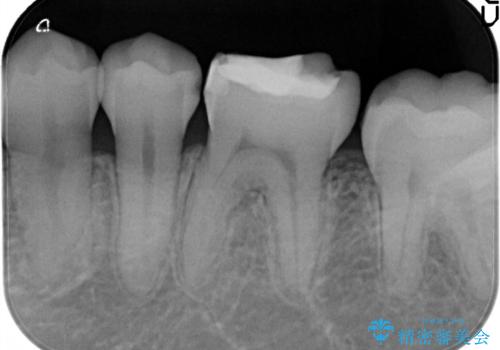

- 定期検診において虫歯を見つけた患者様です。

セラミックインレーにて修復治療をしています。

当院のセラミックインレーはすべてプレスという製法で製作しております。削り出しのものより精度が高く製作可能です。